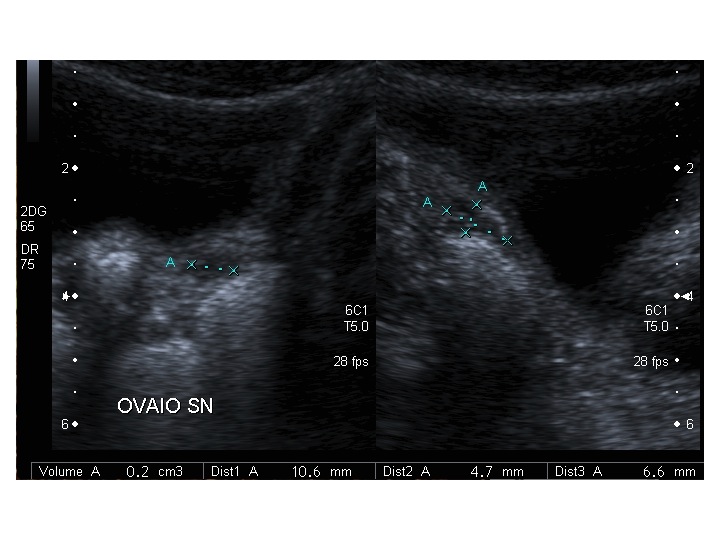

All’ecografia pelvica si osservano le ovaie a “banderella” (figura) e il cariotipo rivela l’assenza di un cromosoma X o la presenza di un mosaicismo, 45 X0/46XX nella forma più comune; nel 5% dei casi di ST può essere presente un frammento di cromosoma Y.

Dopo l'induzione di pubertà è ben visibile la rima endometriale (nella paziente 2 era appena accennata anche nelle immagini pre-terapia), soprattutto nelle sezioni longitudinali, con l'assenza di follicoli a livello ovarico